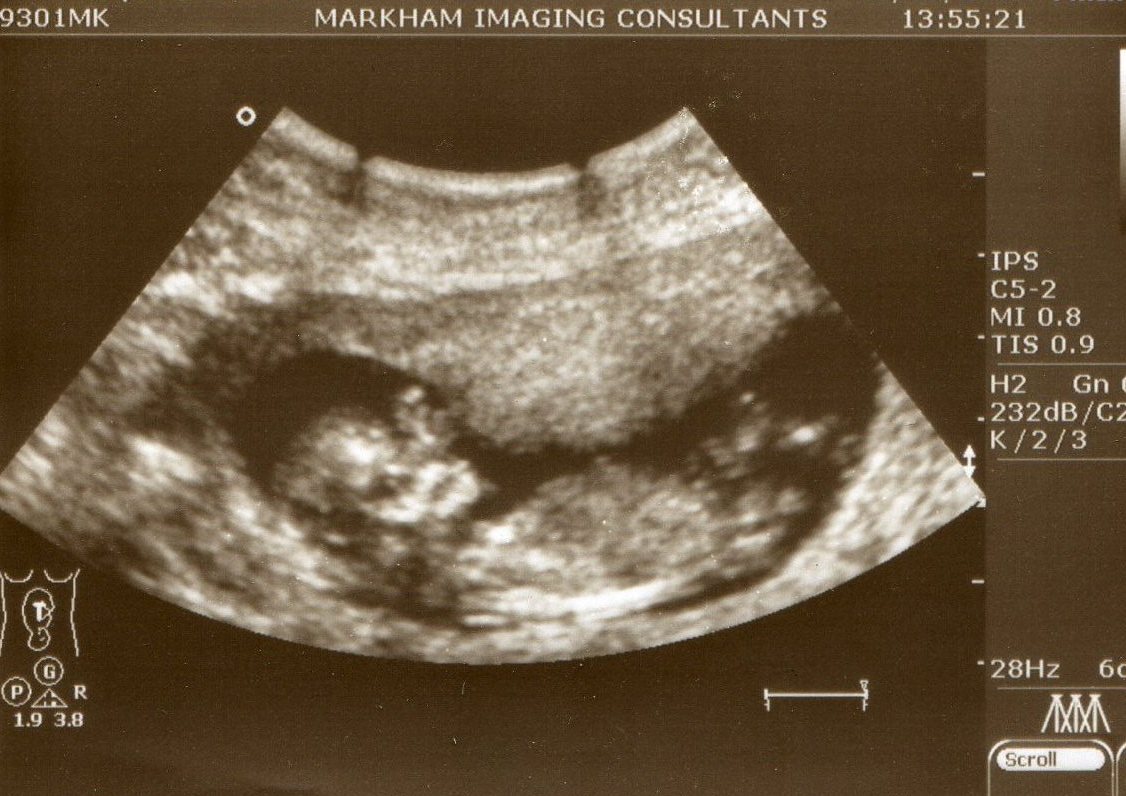

Firstly (and foremostly?) the baby isn't breech. So let's all breathe a sigh of relief there. Whew...

Now - check this out...

Isn't that the most GIRLY little foot you ever did see? :) Yes - we have another itty-bitty girl joining our family - woot woot! We're both over the moon (of course) and so happy to finally know. Would love to share other pics, but she was playing shy - and by shy, I mean, planted face-down into my pelvis - so there was no chance to get a profile view at all.

But since I'm such a brilliant mommy and documented all the scans thus far (erm, or not) - I thought I'd share a few of the past ones...

Here's the 11wk scan - where she's just a little peanut:

And here's a pic of one of the 20wk scan pics - another side profile with a little hand...